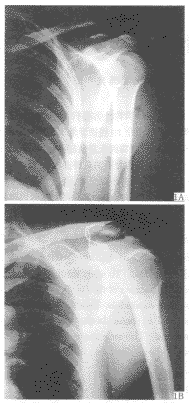

【摘要】 目的 探讨锁骨外侧端不稳定骨折的手术治疗方法及疗效。方法 钢丝环绕锁骨、喙突固定,不暴露骨折端,治疗16例锁骨外侧端不稳定Ⅱ型骨折。结果 随访6~18个月,无畸形愈合、延迟愈合及不愈合 ......